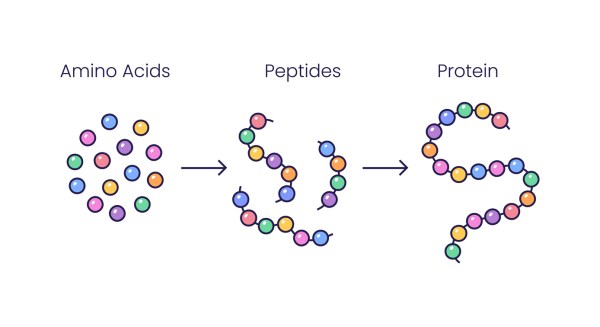

What Are Peptides?

Peptides represent small chains of amino acids, typically containing fewer than 20 of these protein building blocks linked together. When amino acid chains extend beyond this threshold of 20 units, they are generally classified as proteins. Proteins have more complex structures and functions. In the body, peptides serve as molecular messengers, facilitating intercellular communication that promotes cellular healing, extends cellular longevity, and enhances overall cellular performance. Their ability to signal like this enables peptides to initiate repair processes throughout the body. As a therapeutic agent, peptides send signals that interact with target cells. They can substitute for naturally occurring peptides or mimic their actions, modifying the body’s biochemical processes. This communication allows peptides to stimulate regenerative processes and support tissue reconstruction.